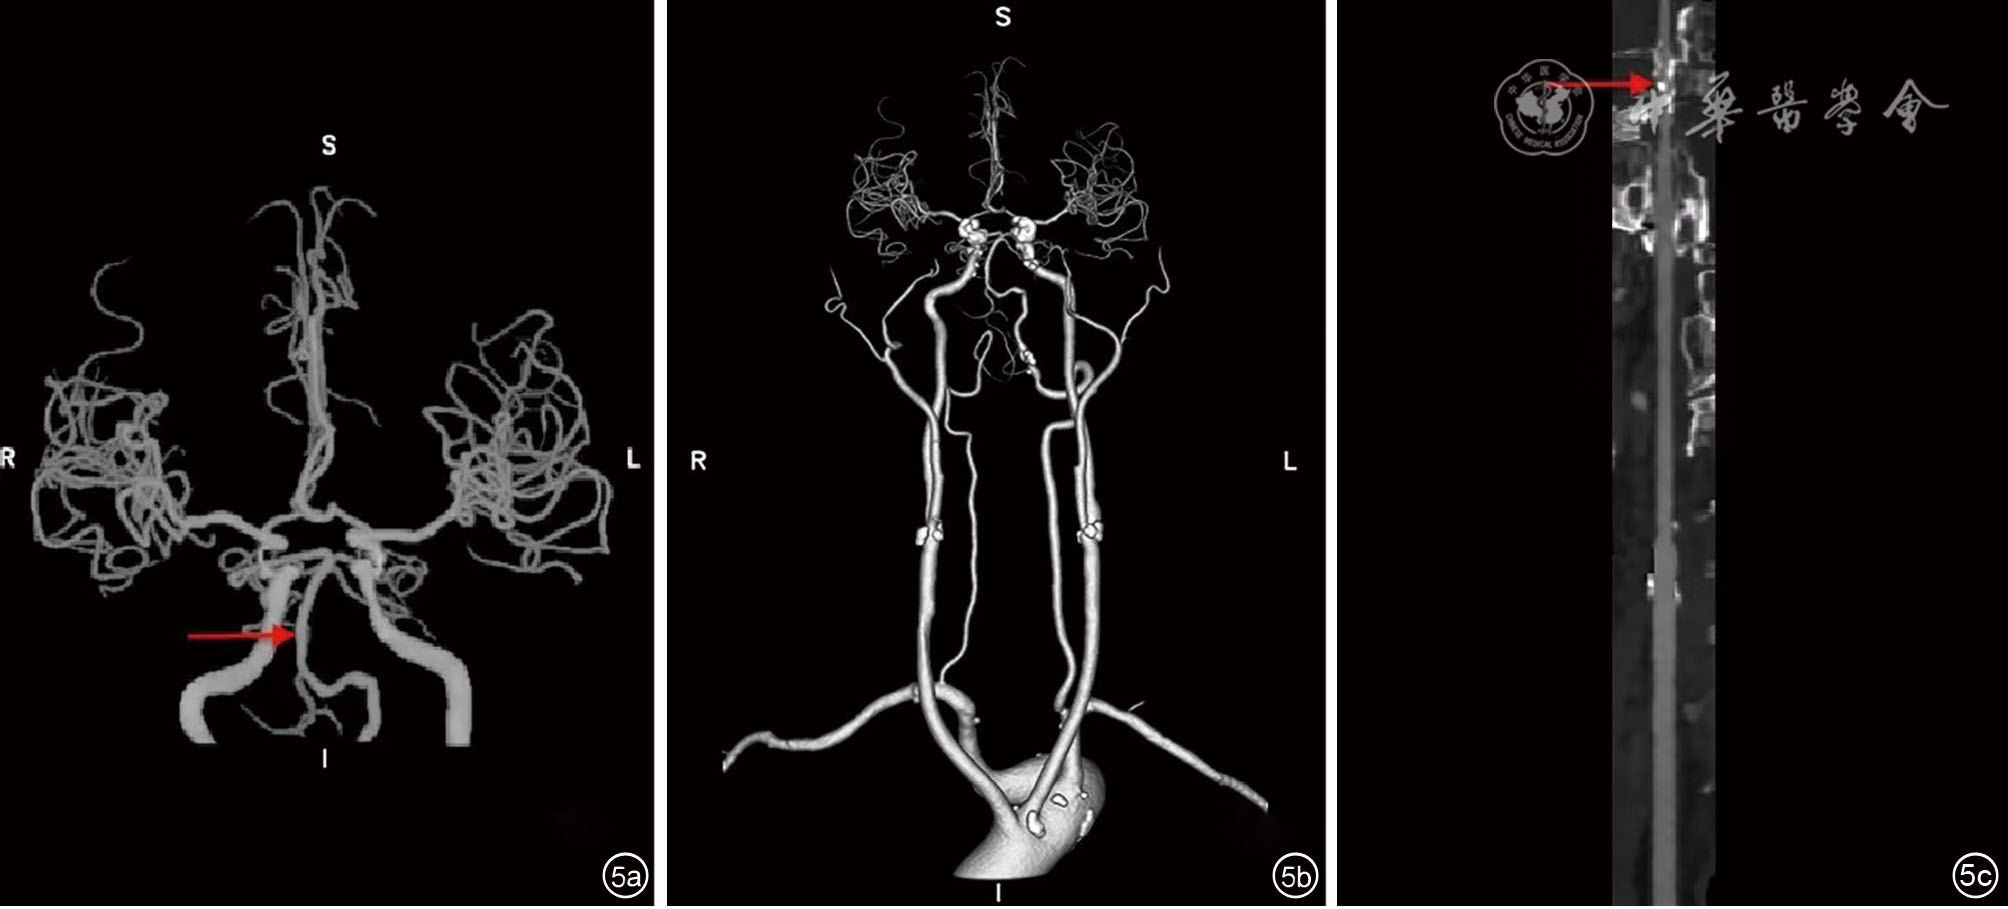

Case report on early acupuncture combined with rehabilitation training dysphagia after endovascular therapy for acute posterior circulation infarction

Bincong Zhao, Yali Wen, Xu Ji